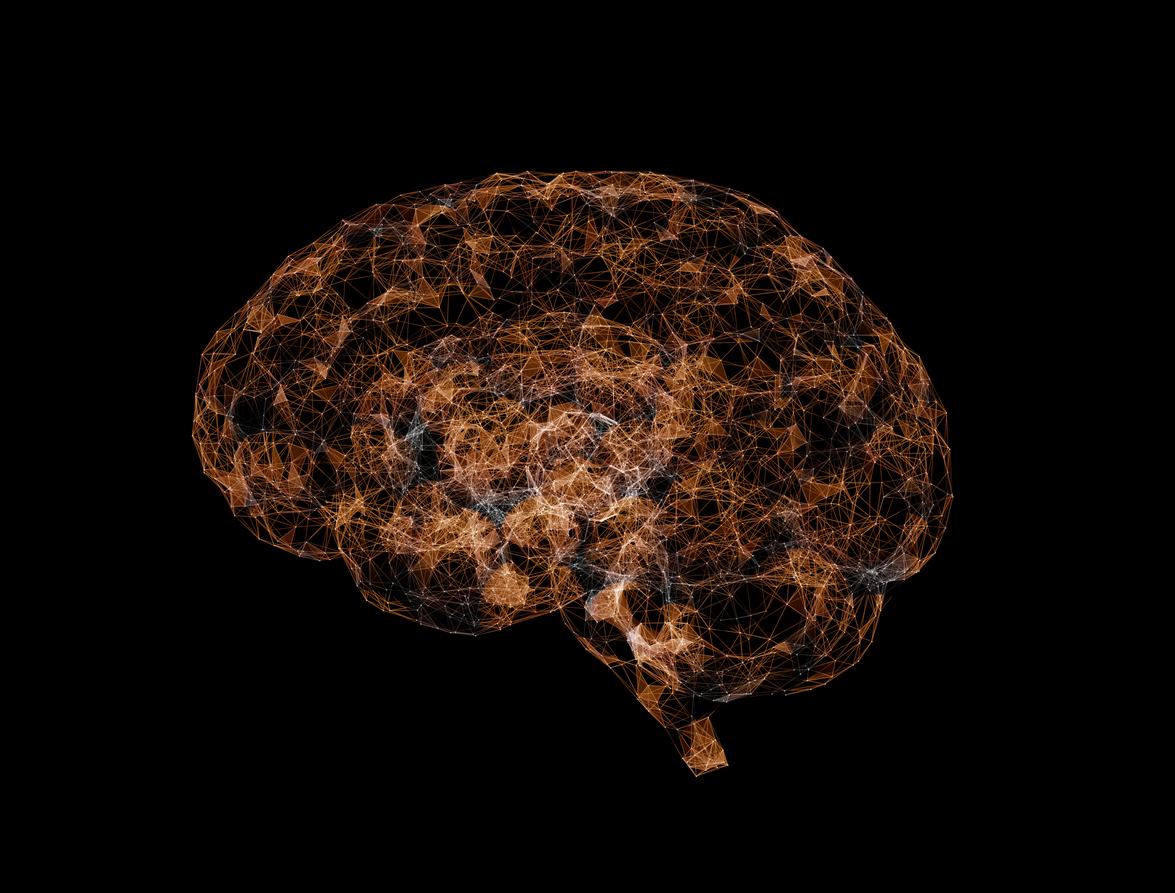

A team of researchers has managed to identify the key areas of the brain where the first cellular changes related to aging appear.

- Researchers in the United States have produced a detailed cell atlas of brain aging by analyzing millions of cells in young and elderly mice.

- They discovered that certain cells, including glial cells and hypothalamus neurons, are undergoing major changes with age. Immune activity increases and myelin producing cells see their effectiveness reduced.

- These alterations affect essential functions such as metabolism and sleep. Although carried out in mice, this research offers a basis for developing therapies against human brain aging.

What if we could precisely identify the place where aging begins in the brain? It is the successful bet by researchers from the Allen Institute, in the United States, who have just produced the first detailed cellular atlas of brain aging. By studying millions of individual cells, they managed to highlight the key areas where the first age -related changes appear.

Precise cartography of brain changes

The brain can be compared to a huge metropolis, made up of thousands of “districts”, each populated by cells with specific functions. Until now, a precise census of the evolutions of these districts were lacked over time. The new study, published in the journal Naturefills this vacuum by examining cells taken from young (2 months) and elderly (18 months) mice – age groups equivalent to human brains of young adults and mature adults.

By analyzing 16 regions of the brain (representing about 35 % of its total volume) scientists identified 847 types of distinct cells. They discovered that certain populations, including support cells called glial cells, were particularly sensitive to aging. These changes appeared mainly around the third ventricle, in the hypothalamus, an area which controls essential functions such as hunger, body temperature, sleep and hormonal production.

As the brain is aging, its immune activity is intensifying, in particular in microglial cells, responsible for cleaning and brain immune defense. The macrophages associated with the borders of the brain also have increased inflammatory activity. These changes suggest that these cells must work harder to maintain brain health with age.

A roadmap for future therapies?

That’s not all: aging also affects cells that produce myelin, this essential insulating substance for communication between neurons. Like a poorly protected electric wire, these neural circuits may work less effectively.

The researchers have finally identified specific groups of neurons in the hypothalamus, responsible for the regulation of appetite, metabolism and energy consumption, which undergo drastic modifications with age. This also corroborates studies linking food factors such as intermittent fasting or caloric restriction to longevity.

“Aging is the main risk factor for devastating diseases such as Alzheimer’s, explain the researchers in a press release. These results offer a detailed card of brain cells most vulnerable to aging. “ This discovery could open the way, according to them, to new therapies to preserve brain health throughout life.